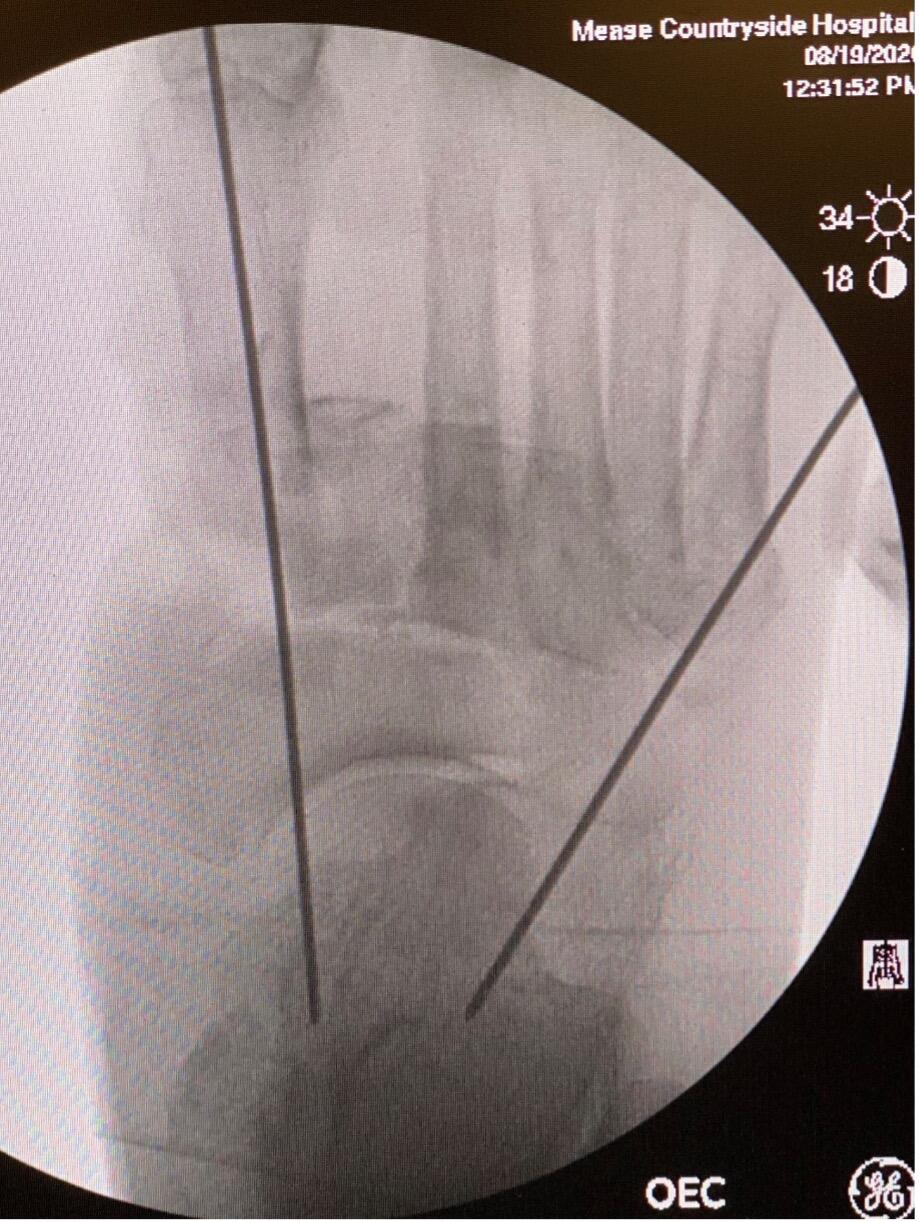

Despite the compromise of the soft tissue envelope structural integrity, it was necessary to make multiple incisions to achieve relative reduction. There were three incisions in total: the first incision along the medial column; the second lateral to the second metatarsal base; and the third between the fourth and fifth metatarsal bases. Even with this adequate exposure, the foot could not adequately reduce in the sagittal plane. Multiple osteotomies across the tarsometatarsal joint with overall shortening achieved the desired reduction. Temporary pinning maintained position.